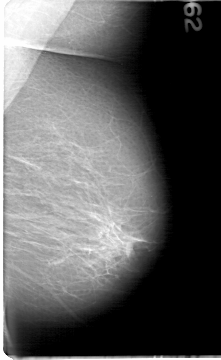

D_4081_1.RIGHT_MLO

ics_version 1.0

filename D-4081-1

DATE_OF_STUDY 20 12 1993

PATIENT_AGE 59

FILM_TYPE REGULAR

DENSITY 2

DATE_DIGITIZED 10 5 1999

DIGITIZER HOWTEK 43.5

LEFT_MLO LINES 5386 PIXELS_PER_LINE 3301 BITS_PER_PIXEL 12 RESOLUTION 43.5 NON_OVERLAY